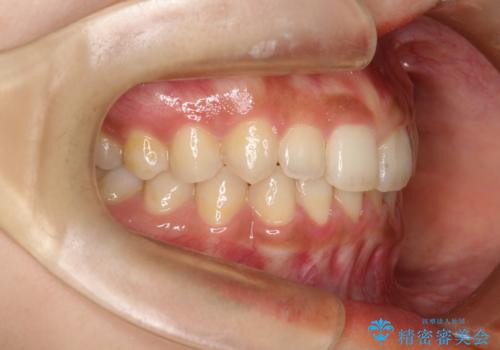

- 前歯のガタガタを主訴に来院された患者様です。

八重歯になっており、下顎の前歯が上顎の前歯に隠れてしまう、ディープバイトという状態でした。

インビザラインを使用して矯正する計画としました。

ディープバイトの場合、ワイヤー装置の装着が難しいことがあります。

インビザラインではかみ合わせに左右されず装着できるメリットがあり、ワイヤーに比べインビザラインの方が治療しやすい場合もあります。